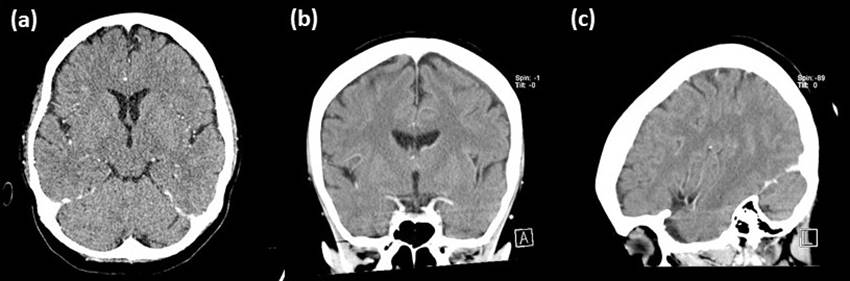

Figure 1: Pre-treatment computed tomography showing left subdural collection. (a) axial view, (b) coronal view and (c) sagittal view.

Figure 2: Interval computed tomography 2 weeks after treatment showing marked improvement of left subdural collection. (a) axial view, (b) coronal view and (c) sagittal view.

A 31-year-old lady, gravida 3 para 2 at 34 weeks of gestation with twin pregnancy initially presented with labour pain. Antenatally, this was an uneventful pregnancy. Cardiotocography (CTG) at presentation was reactive for twin 1. CTG for twin 2 showed poor beat to beat variation with no acceleration. She was then posted for emergency lower segment caesarean section (LSCS) for foetal distress. She was given intravenous ampicillin-sulbactam 1.5g as prophylactic antibiotic. Skin disinfection was done under aseptic technique. Subarachnoid block was done at L3 level after 2 attempts. Intrathecal fentanyl 15mg and 1.9ml of bupivacaine 0.5% were given. Five minutes post spinal anaesthesia, patient developed high spinal symptoms with sudden onset back pain and shoulder numbness. She was resuscitated with intravenous ephedrine, phenylephedrine and fluid. The patient subsequently responded and managed to go through the surgery. On post operation day 2, patient complained of severe headache, associated with neck stiffness and fever. There was no cough, no diarrhoea, no vomiting or dysuria. Her level of consciousness was normal. Upon examination, the blood pressure was 108/60mmHg, pulse rate was 98 beats per minute and temperature was 40oC. Full blood count indicated haemoglobin level was 8.6g/dl, white blood cell count was 12.9x109/L and platelet count was 291x109/L. Renal profile was normal. Bicarbonate level was 11.9mmol/L (Table 1). She was then admitted to intensive care unit and intubated for respiratory distress. At the same time, she was given intravenous 2g of meropenem three times a day for suspected post spinal meningitis. Subsequently, she undergone contrast enhanced computed tomography of the brain which showed meningeal enhancement with left fronto-parietal subdural collection with maximum thickness of 5mm (Figure 1). We then performed a spinal tap on the following day. No cells were seen during CSF examination, total protein level was 0.21g/dl and glucose ratio was normal. Both CSF cultures and latex agglutination test were negative. She was then treated with 6 weeks of intravenous ceftriaxone 2g twice daily. Interval CT scan of brain showed marked improvement (Figure 2). Eventually, she recovered.

Post spinal subdural hematoma (SDH) is another differential diagnosis. SDH is presumed to occur due to reduced intracranial pressure following cerebrospinal fluid (CSF) loss, causing decompression of brain leading to rupture of fragile bridging veins [5]. In our patient, the point against this diagnosis is the measured Hounsfield Unit is not suggestive of hematoma and SDH usually does not present with sepsis syndrome.

We think our patient had post spinal meningitis with subdural collection because she presented with sepsis syndrome post operatively that required ICU admission. Computed tomography of brain supported the diagnosis of subdural collection and she responded well to antibiotic therapy. Her CSF appeared sterile probably due to prior administration of antibiotic a day before the lumbar puncture.